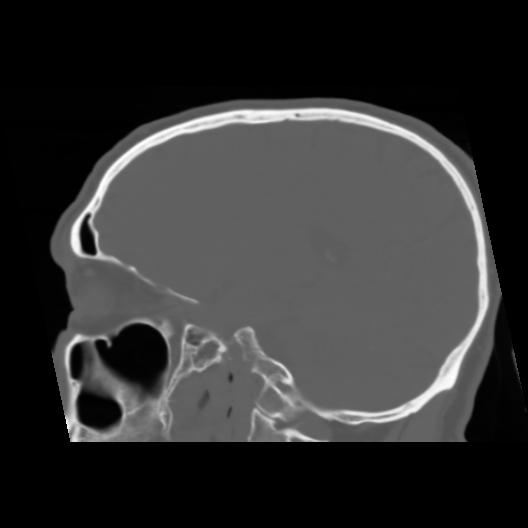

6 CEREBRO,,Sagittal,3.000,CEREBRO,Sagittal,